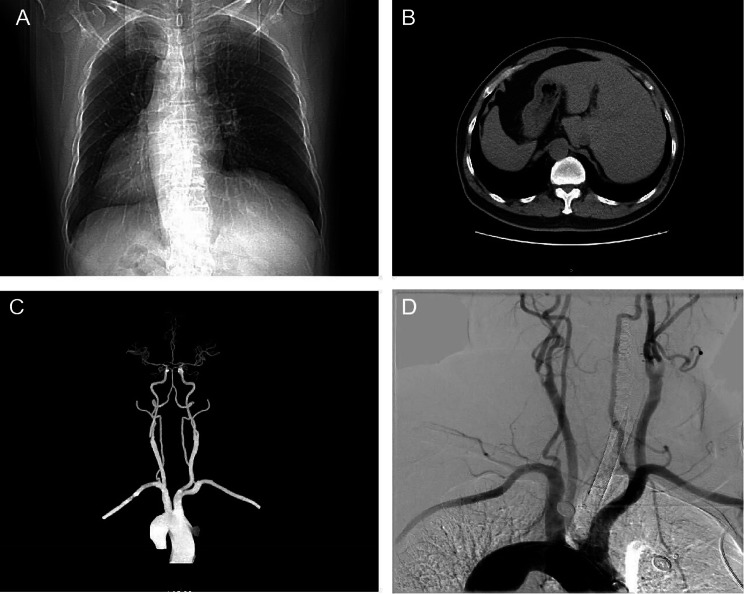

A 68-year-old right-handed man, who had a history of hypertension, was hospitalized owing to carotid stenosis found one month before. The patient’s carotid artery ultrasonography showed severe stenosis of the right carotid artery (stenosis is over 70%). Current guidelines state that medical therapy is sufficient for the treatment of carotid artery stenosis below 50% [9]. However, if stenosis is over 50% in symptomatic patients and over 70% in asymptomatic patients, surgical or endovascular methods are recommended [10]. The most common complications of carotid stenting are embolic infarcts, prolonged hypotension/bradycardia, and hyperperfusion syndrome [10]. Interestingly, during carotid ultrasonography, it was found that the heart was on the right side. Figure 1 illustrates how computed tomography (CT) and digital subtraction angiography (DSA) further confirmed the patient’s SI (Fig. 1A, B, C and D).

Fig. 1.

CT and DSA images of SI patient. (A) Chest CT image showing the heart on the right side. (B) Abdominal CT suggesting left–right viscera inversion. (C) Brain CTA image showing that the aortic arch vessels in the patient are reversed from side to side. (D) DSA image showing that the aortic arch vessels in the patient are reversed from side to side. SI: situs inversus; CT: Computed tomography; DSA: Digital subtraction angiography; CTA: Computed tomography angiography